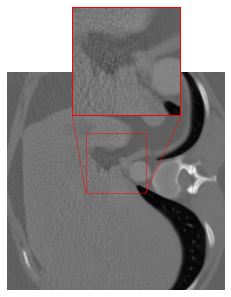

However, our application of this strategy in CT results in artifacts (cf. Figure 1(c)) at the patch boundaries, showcasing a sudden shift from intense to subtle smoothing with the cropping strategy. A reason for this might be that the errors are typically not Gaussian white noise, but more involved. For mitigating the artifacts, we modify the cropping approach of [47] by implementing padding in the output of the FBP to align with the network architecture. The DRUNet architecture operates solely on images sized as multiples of due to its four downsampling steps, whereas the LoDoPaB-CT dataset comprises images of size , which does not conform to this requirement. To address this, we apply mirror padding to enlarge the images to before passing them through the network and subsequently cropping them back to the original size of Figure 2 illustrates the suitability of the proposed strategy. (We point out that the image depicted in Figure 2 represents one of the most challenging reconstructions within the dataset.)

Effectiveness of the Rotational Augmentation

To evaluate the impact of rotational augmentation, we conducted an experiment by training two networks: one with rotational augmentation and the other without. The objective was to investigate the network’s response to input images under different orientations. Specifically, we applied two scenarios: firstly, inputting images as they are, and secondly, rotating them by 90° before feeding them into the networks. Results depicted in Fig. 3 illustrate a noteworthy observation. For the network with rotational augmentation during training (cf. 2(e) and 2(f)), the output remains consistent regardless of the input image’s orientation. However, for the network trained without rotational augmentation (cf. 2(c) and 2(d)), the output varies between the normal and rotated input scenarios. This experiment highlights the effectiveness of rotational augmentation in achieving network equivariance and ensuring consistent performance across different orientations of input images.